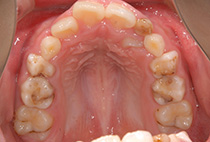

ガタガタの歯並びを気にして兄弟で来院されました。お二人とも歯の大きさに対して上下とも顎が小さくこのままでは八重歯や出っ歯になってしまう歯並びです。

上顎を急速拡大装置で拡大し下顎はリンガルアーチで拡大し歯の生えるスペースを作ってあげることにしました。

上下顎とも横に拡大してきたので歯の生えるスペースができてきました。骨が成長しスペースができると歯は自然に並びだします。左上の内側に入っていた歯もきれいに並んできました。

今後永久歯が生え揃うまで、定期健診で様子を見る必要はあります。犬歯が生える時期にもう一度顎を広げるとブラケットをつける全顎矯正は必要なさそうです。